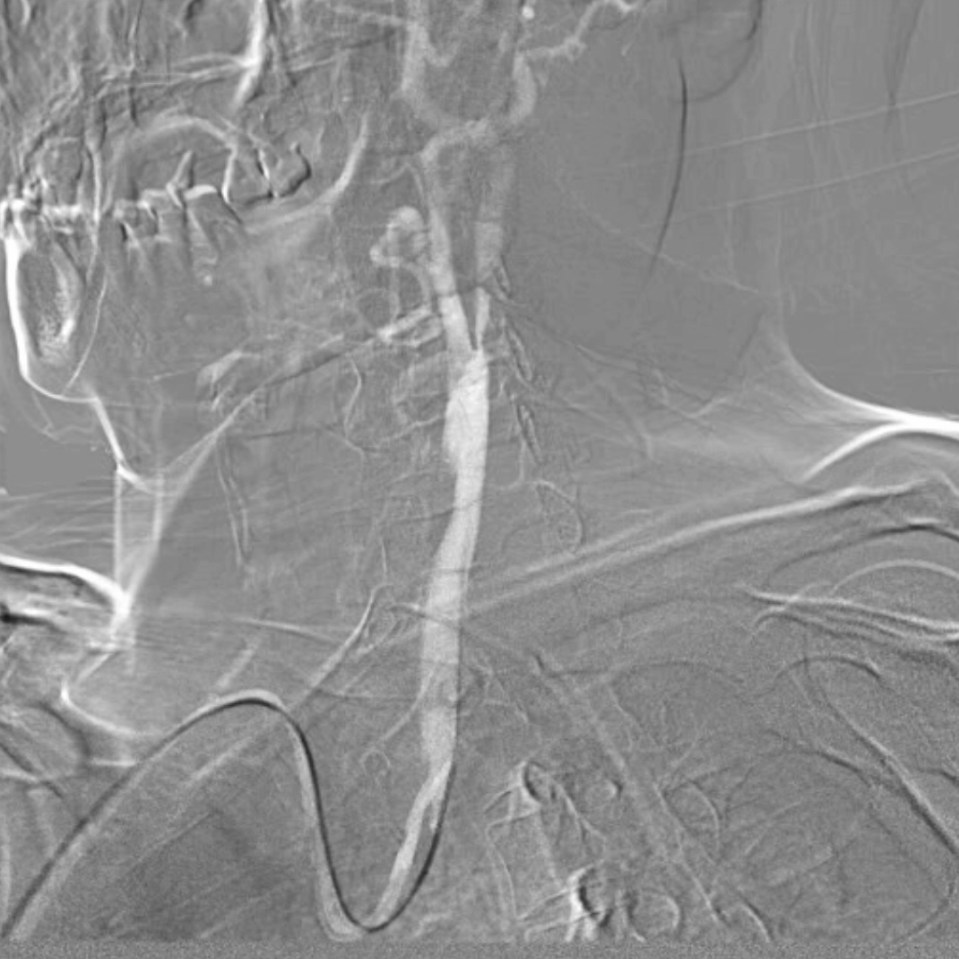

血供改善与安全性验证

造影显示:支架膨胀良好,无需后扩张;

颅内血供:左侧颈内动脉血流通畅,因右侧闭塞,左侧成为全脑主要供血通路,血供恢复满意